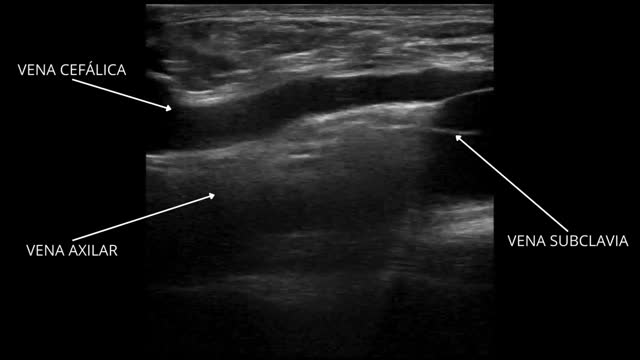

A 33-year-old male was admitted to the Intensive Care Unit due to respiratory distress secondary to Legionella pneumonia, requiring neuromuscular block and prone decubitus upon admission. We conducted prior ultrasound-guided catheterization of the right cephalic vein at its final portion where the vessel drains into the subclavian vein. The Fig. 1 and Video 1 show a longitudinal view of the catheter guide crossing the junction of the cephalic and axillary veins towards the right subclavian vein. Correct positioning was confirmed radiographically (Fig. 1). Such catheterization offers an ultrasound-guided alternative to the infraclavicular subclavian vein, which is not always accessible to ultrasound, posing an increased risk of pneumothorax that should be avoided in patients with severe respiratory failure. On the other hand, positioning is more accessible during prone decubitus compared with other venous accesses (Supplementary images).